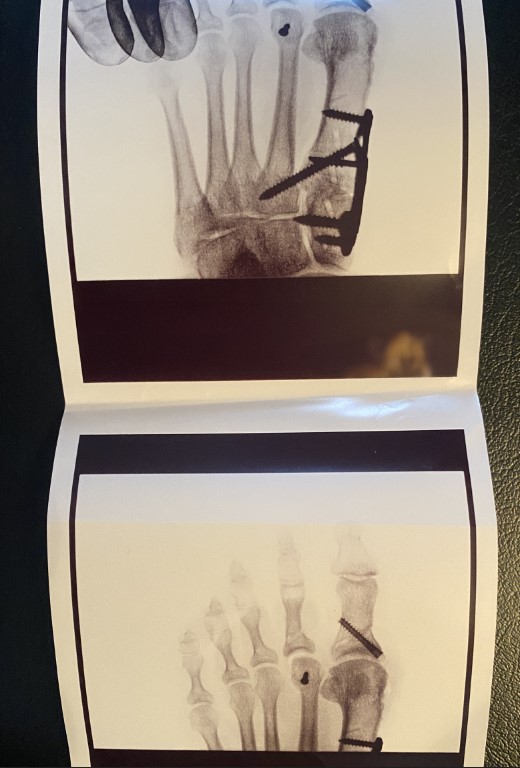

Dr. Cody performed bunion surgery on both of my feet (2 years apart). It was an excellent experience and I would highly recommend Dr. Cody to anyone suffering with foot or ankle issues. She is a highly skilled surgeon and very compassionate.

I have lived with foot pain and bunions my entire life - I had previous surgeries to address these issues, however the pain persisted and physical deformities came back. I did a lot of research before choosing a foot specialist and I am thrilled with my results with Dr. Cody!

Bunions